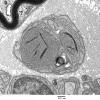

PERIPHERAL NEUROPATHY

5 AXONAL REGENERATION (6)